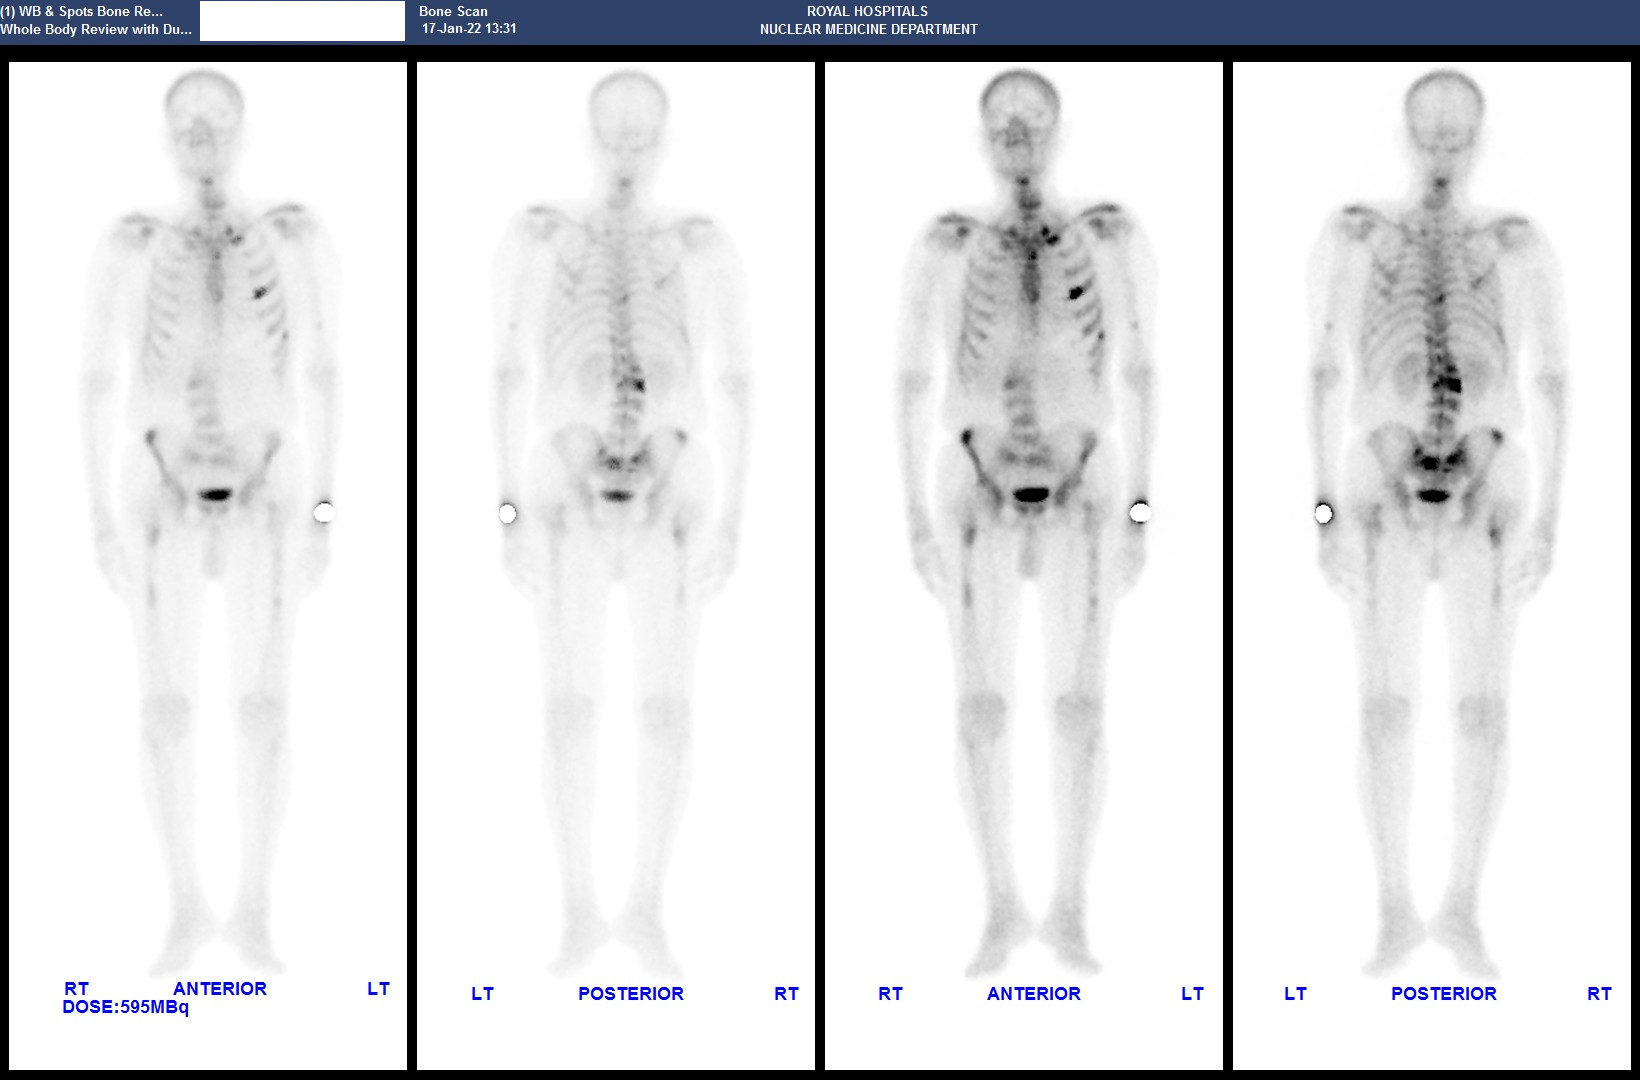

Whole body bone scintigraphy

Later on, the patient had a whole body bone scintigraphy which showed widespread bone metastasis.